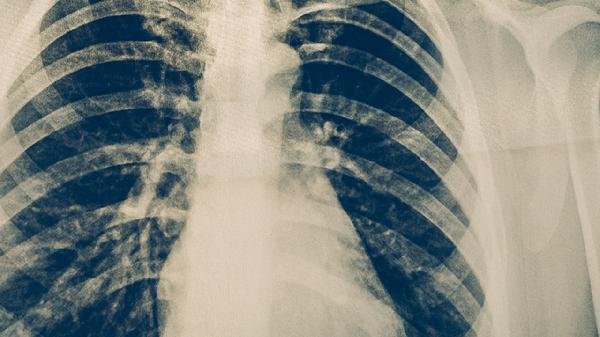

肺結(jié)核病的主要癥狀包括持續(xù)咳嗽、咳痰、低熱、盜汗、體重下降和疲勞,嚴(yán)重時(shí)可能出現(xiàn)咯血。若出現(xiàn)這些癥狀,尤其是持續(xù)咳嗽超過(guò)兩周,應(yīng)及時(shí)就醫(yī)進(jìn)行專業(yè)診斷和治療。

肺結(jié)核是一種嚴(yán)重的傳染病,早期診斷和治療至關(guān)重要。若出現(xiàn)上述癥狀,尤其是持續(xù)咳嗽超過(guò)兩周,應(yīng)及時(shí)就醫(yī),進(jìn)行胸部X光、痰液檢查和結(jié)核菌素試驗(yàn)等專業(yè)診斷。治療肺結(jié)核通常需要長(zhǎng)期服用抗結(jié)核藥物,如異煙肼、利福平和吡嗪酰胺,療程通常為6至9個(gè)月?;颊邞?yīng)嚴(yán)格遵循醫(yī)囑,按時(shí)服藥,避免中斷治療,以防止耐藥性的產(chǎn)生和疾病的復(fù)發(fā)。同時(shí),保持良好的生活習(xí)慣,如均衡飲食、適量運(yùn)動(dòng)和充足休息,有助于提高治療效果和身體恢復(fù)。